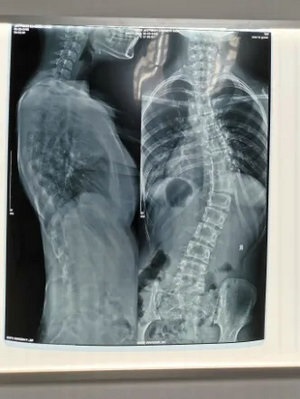

脊柱侧弯是指脊柱在冠状面、矢状面、水平面发生的三维骨骼畸形。X线诊断Cobb角超过10°,即可诊断为脊柱侧弯。患者会出现双肩不等高、腰或背部一侧隆起、对侧凹陷、胸廓畸形等外观改变,并会导致严重的身心健康问题。目前,脊柱侧弯已成为继肥胖症、近视之后我国儿童青少年健康的第三大“杀手”,防控形势严峻,主要表现在:

1.脊柱侧弯筛查需站立位全脊柱X光片正侧位。

2.骨盆前倾:矢状面 Cobb 角>50°。